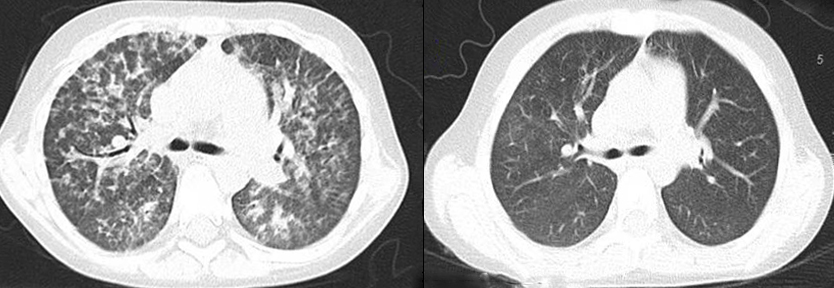

移植后,童童的随访结果显示,噬血细胞综合征表现迅速缓解,系统性红斑狼疮和肺泡蛋白沉积症的症状显著改善,肝脾明显缩小,代谢、免疫方面各项指标陆续从增高上百倍恢复到正常水平。

童童术前(左)和术后(右)CT对比,肺泡蛋白沉积症状显著改善。

今年是童童移植后第4年,在减停激素及免疫抑制药物后,童童病情没有复发,也没有严重的移植相关排斥反应,身体状况始终平稳。更令人惊喜的是,童童的身高发育也开始追赶同龄人,她已经完全回归正常的生活。